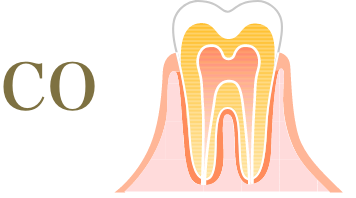

むし歯の進行度と治療方法

-

歯の表面が少し溶け、虫歯になりかけの状態。

痛みは感じず、認識しにくい状態。- 治療方法

- 適切な歯磨きや

フッ素塗布で自然治癒